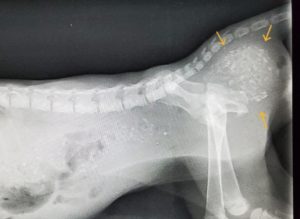

レントゲンを撮影すると、盲端になっている大腸に糞塊が停滞していました。

左が術前、右が術後1週間のレントゲン写真です。糞塊が停滞することはなくなりました。